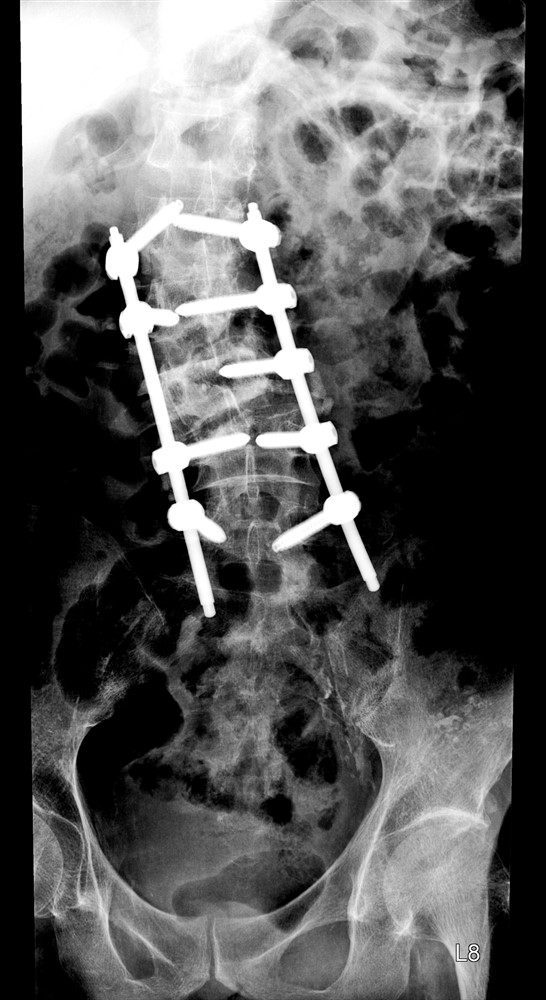

一名六十一歲男性病人因脊椎側彎角度超過四十度,導致脊椎骨嚴重錯位,無法支撐身體,而來求醫。張建鈞醫師表示,嚴重脊椎側彎會導致病人出現腰背疼痛、胸悶、呼吸困難等症狀,嚴重者甚至會導致癱瘓。因此,嚴重脊椎側彎病人動手術治療是必要的。

由於病人屬於大角度脊椎側彎,因此張建鈞醫師採用微創脊椎手術,並使用電腦導航輔助,精準定位脊椎骨錯位定點,並準確打入鋼釘,確保矯正的效果。「微創手術具有創傷小、出血少、恢復快等優點。過程中會在病人皮膚開幾個小切口,讓手術器械和設備透過切口插入體內以進行操作。」病人術後明顯改善脊椎側彎角度,不只能正常行走,腰背疼痛等症狀也緩解。

六十一歲嚴重脊椎側彎病人接受矯正手術治療。